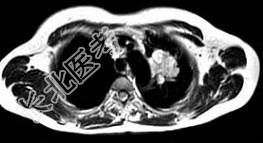

- 单项选择题男,68岁, 声音嘶哑半月,行MRI检查如图, 其最可能的诊断为 ( )

A、右上肺癌

B、左上肺结核球

C、左上肺炎性假瘤

D、左上肺癌

E、左上肺动静脉瘤